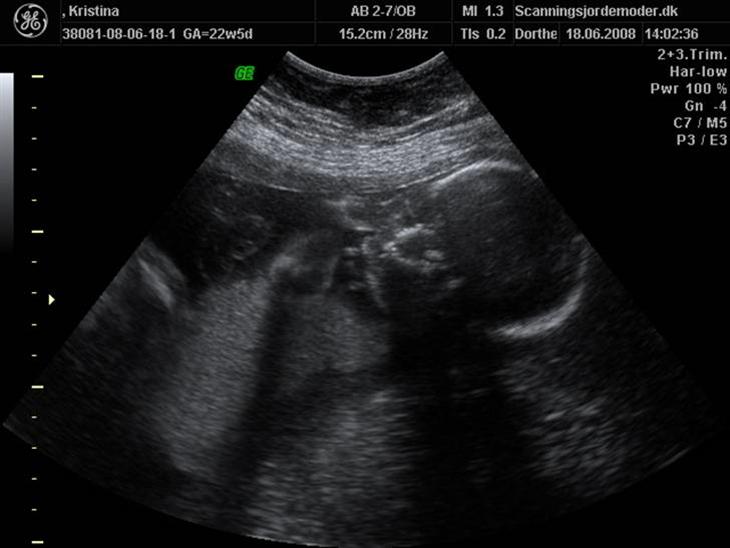

Den 18 juni fik jeg foretaget en kønsscanning, og det er tydeligt at se vi venter os en lillebror til Patrick. :-)

det er en dreng kig billed 14 det er tydligt